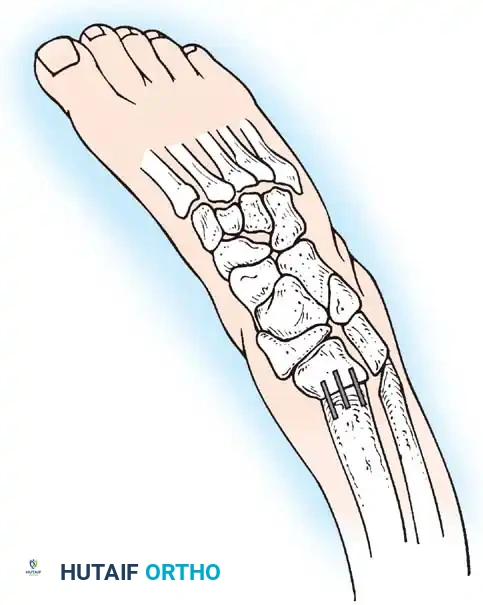

Foot and Ankle Deformities

The primary goal for the foot in myelomeningocele is to achieve a supple, plantigrade, and braceable foot that is free of pressure ulcerations. Due to insensate skin, any rigid deformity will inevitably lead to skin breakdown, osteomyelitis, and potential amputation.

Clubfoot (Talipes Equinovarus)

Clubfoot in myelomeningocele is notoriously rigid and teratologic.

Clubfoot Clinical Presentation

Initial management utilizes the Ponseti method of serial casting. However, the recurrence rate is significantly higher than in idiopathic clubfoot.

Ponseti Casting Technique

When conservative measures fail, surgical intervention is required:

1. Comprehensive Posteromedial Release (PMR): Involves lengthening of the Achilles, posterior tibialis, FDL, and FHL, along with extensive capsulotomies of the ankle, subtalar, and talonavicular joints.